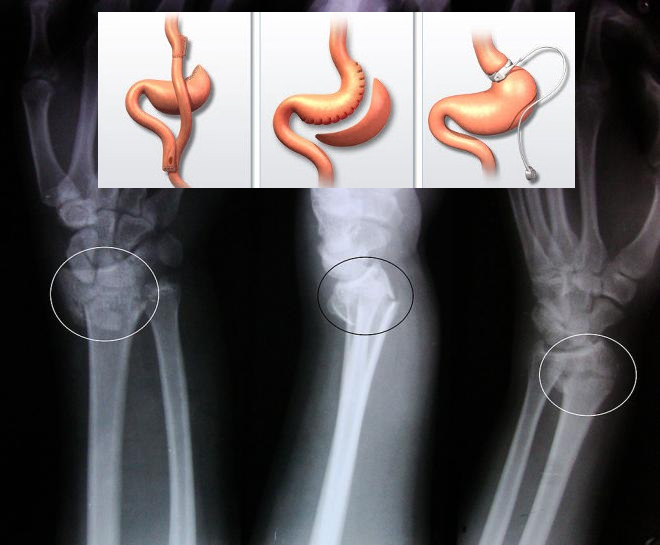

Autorii au studiat datele cu privire la starea de sănătate a 2064 de pacienți supuși intervențiilor bariatrice, în perioada anilor 2001-2009. Ei au analizat, de asemenea și datele cu privire la starea de sănătate a 5027 persoane obeze, care nu au fost supuse intervenției chirurgicale. S-a descoperit că la persoanele care au suferit o intervenție chirurgicală, a crescut cu 21% riscul de fracturi, timp de cinci ani după aceasta. Fracturile au fost mai frecvente la persoanele supuse intervențiilor cu malabsorbție, adică ce împiedică absorbția alimentelor. La acești pacienți, riscul de fracturi este cu 47% mai mare și această cifră a rămas ridicată timp de 12 ani după operație. Cele mai frecvente fracturi sunt cele de os radial, ulnar, humerus, femur și tibie.